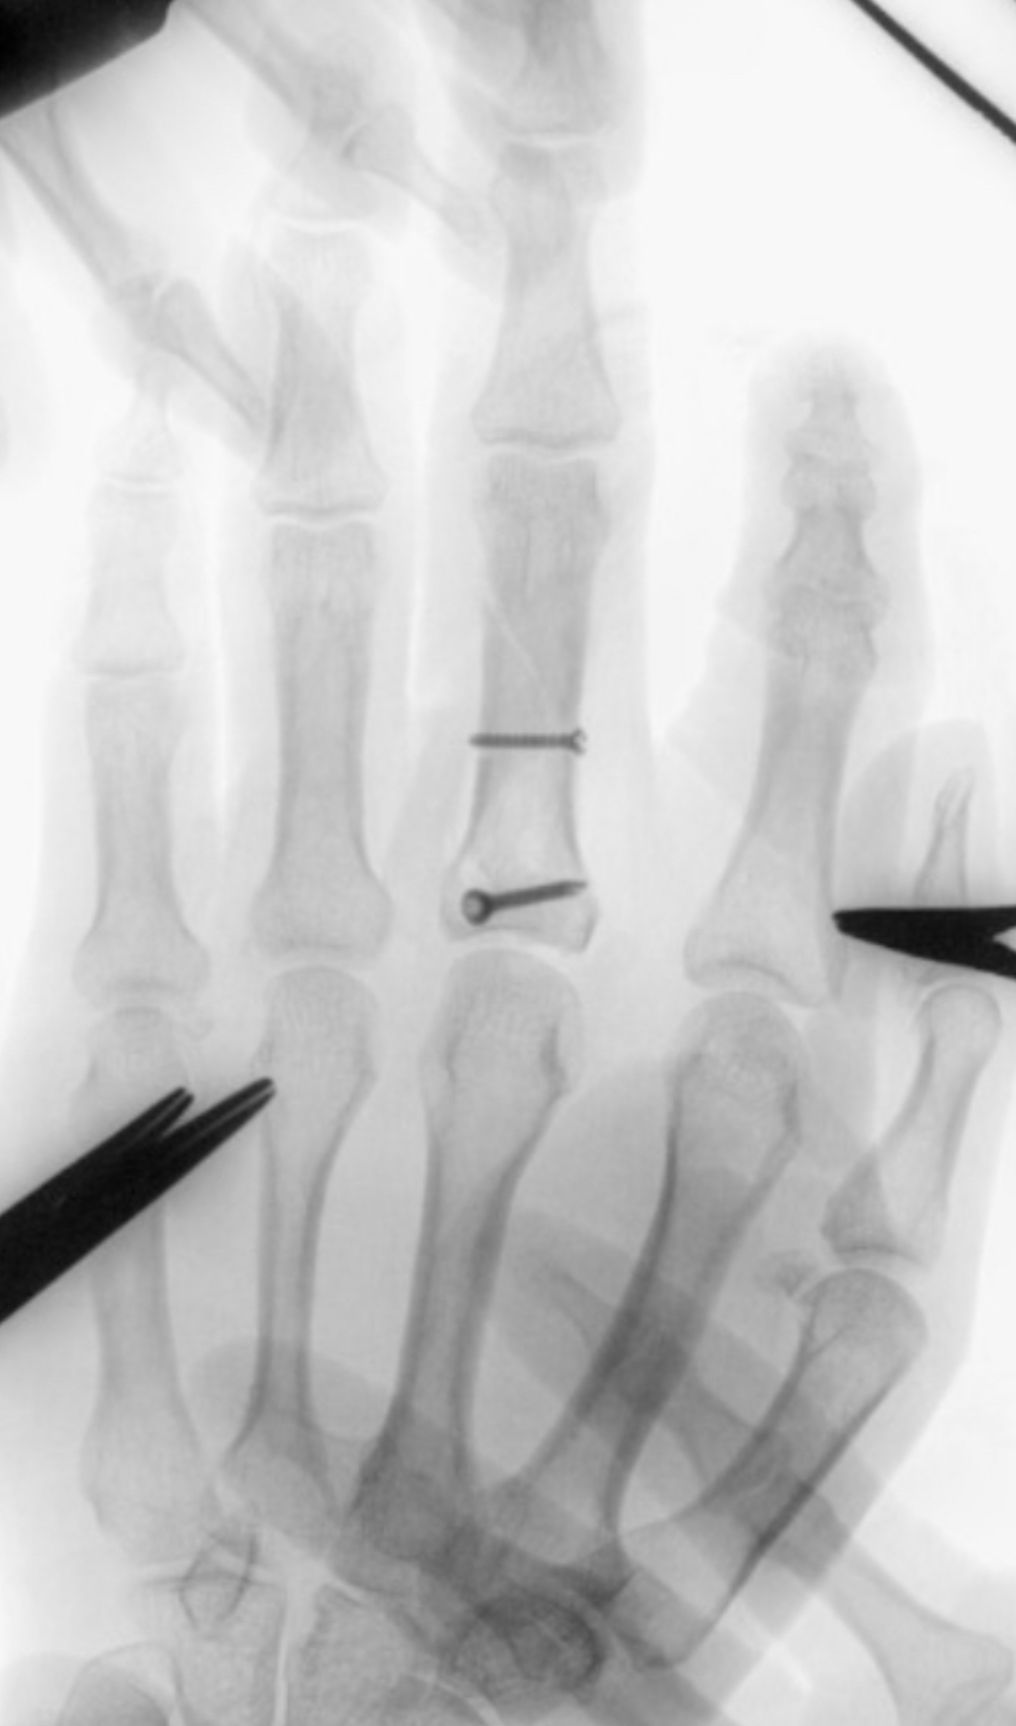

Fotos y videos